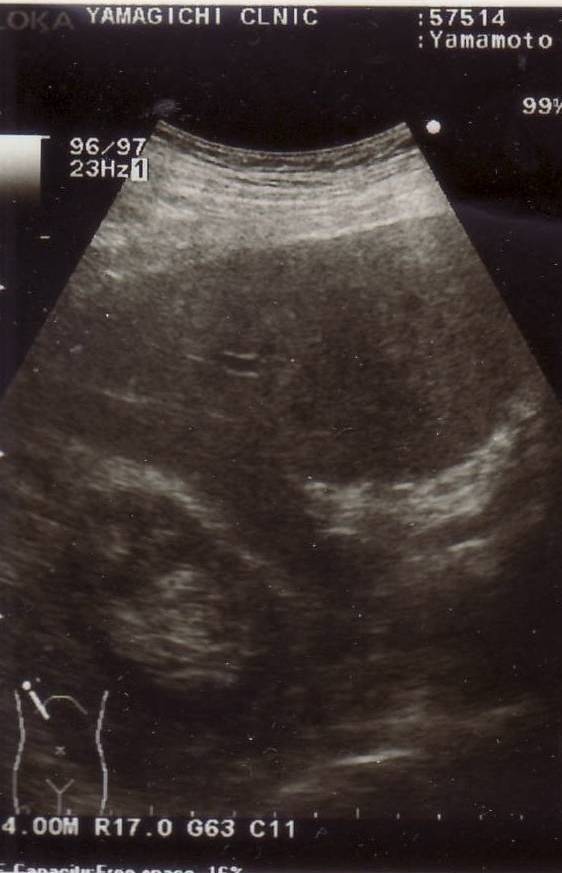

石が尿管に詰ま

り腎臓が尿で

浸潤した

2014年8月6日

(水)

腎臓が正常に

なった

2014年9月11日

(木)

僕の腎臓の超音波映像

偶然ですが、除菌5日目に右脇腹が猛烈に痛んだので、緊急に山口先生に見ていただき、腹部レントゲン撮影と超音波検査により、 何と、尿管結石にょうかんけっせきも発症したことが分かりました。 結石が尿管に詰まって、右図下左の超音波による腎臓じんぞうの画像のように、 腎臓が尿で浸潤しんじゅんしたのです。 この治療も投薬にてピロリ菌除菌と同時進行となりました。数日後に尿管結石は完治しました。その超音波画像が右図下右の腎臓画像で、正常になっています。 ピロリ菌の除菌の最中に、偶然、尿管結石を発祥するという不可思議なことでした。